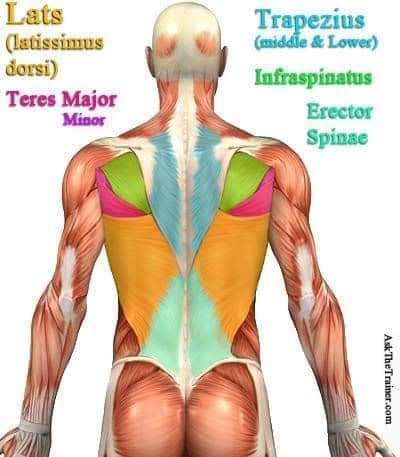

Спинні м'язи

Спинні м'язи виконують функції підтримки хребта, а також дозволяють здійснювати рухи тулуба.

Поверхневі спинні м'язи

М'язи, що піднімають лопатку: Трапецієподібний м'яз: великий м'яз, що покриває верхню частину спини. Його функція - підтримка і рух лопаток, а також забезпечення стабільності хребта.

М'язи, що ведуть лопатку до хребта: Широкий м'яз спини: великий м'яз, що розташований в нижній частині спини. Він відповідає за рухи плечей і лопаток, а також за розширення верхньої частини тулуба.

Глибинні спинні м'язи

М'язи, що забезпечують стабільність хребта: М'язи, що розташовані між хребцями: включають мускулатуру, яка забезпечує стабільність і підтримку хребта, а також дозволяє здійснювати рухи хребта.

М'язи, що здійснюють ротацію та нахили

М'язи, що забезпечують ротацію хребта: Ротаційні м'язи: допомагають у здійсненні обертальних рухів тулуба, а також у підтримці рівноваги і стабільності хребта.